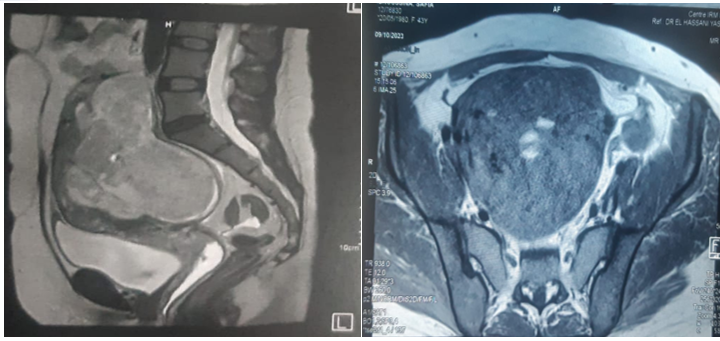

45 years old, single, nulligest, still in a period of reproductive activity, admitted for chronic pelvic pain evolving 6 months ago in a context of conservation of general condition; in whom the examination found an abdominal-pelvic mass reaching the umbilicus measuring 16 cm (fig 1).

Fig 1: Abdominal-pelvic mass arriving at the umbilicus measuring 16 cm

Pelvic ultrasound showed the presence of a bully uterine tissue mass, roughly oval, with lobulated contours, discreetly vascularized on color Doppler measuring 15x9cm.

Abdomino-pelvic CT objectified the presence of an intra-uterine tissue mass lateralized on the left heterogeneously enhanced after injection of PDC, fairly well limited, seat of the area of necrosis, measuring 127x80x165cm. Associated with left external iliac adenopathy of 8 mm Probably related to uterine myoma.

Fig 2: Echographic aspect tissue mass of heterogeneous uterine origin measuring 15 cm

Fig 3: CT appearance of a tissue mass of hetero-dense uterine origin poorly limited in places measuring 15 cm